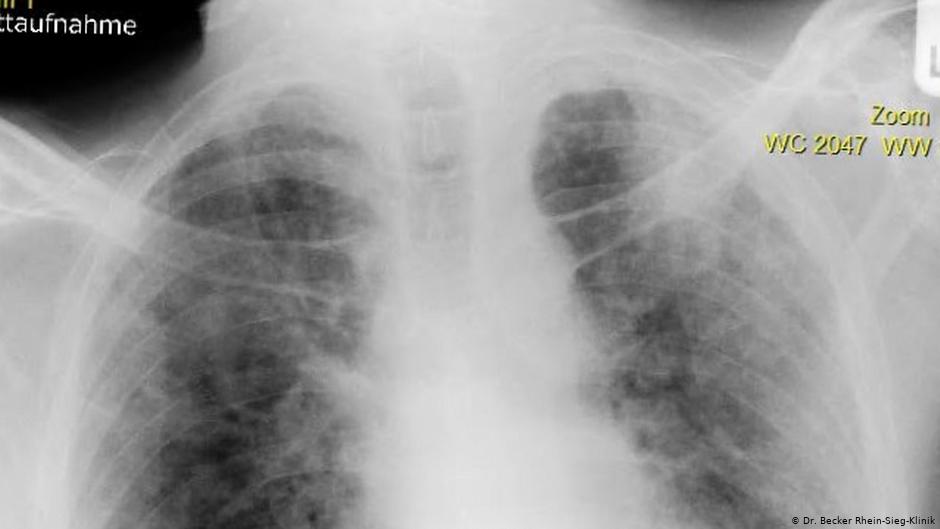

Немец Петер Шмидтген (Peter Schmidtgen) — один из тех, кто перенес COVID-19 в наиболее тяжелой форме. Рентгеновский снимок его легких сейчас показывают друг другу врачи как пример губительного воздействия нового коронавируса SARS-CoV-2 на организм человека.

По ее словам, врачи из других клиник, куда вынуждены были на время перевезти находящегося в коме Шмидтгена, просто теряли дар речи, когда видели снимки его легких. Они были похожи на один большой рубец.